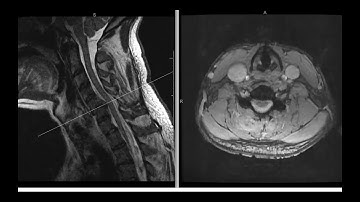

Facet dislocation: unilateral, subluxation, perched, and locked facets